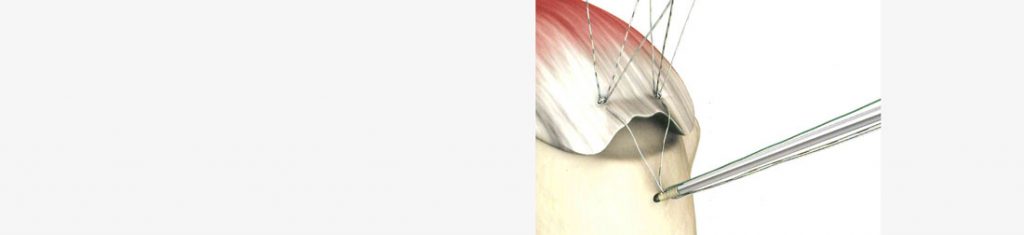

Ob eine gerissene Sehne refixiert werden kann, hängt nicht nur vom Patientenalter, sondern auch von der biologischen Qualität der Sehne ab. Durch eine MRT-Untersuchung kann festgestellt werden, ob im individuellen Fall, eine operative Therapie erfolgsversprechend ist. In der Regel kann durch ein arthroskopisches Operationsverfahren die Sehne mit speziellen Nahtankern reinseriert werden.

Nach dem Eingriff ist die aktive Schultergelenksbeweglichkeit für 6 Wochen eingeschränkt. Intensive physiotherapeutische Maßnahmen begleiten die Rehabilitation, eine Wiederaufnahme der beruflichen Tätigkeit ist nach ca. 3 Monaten möglich.